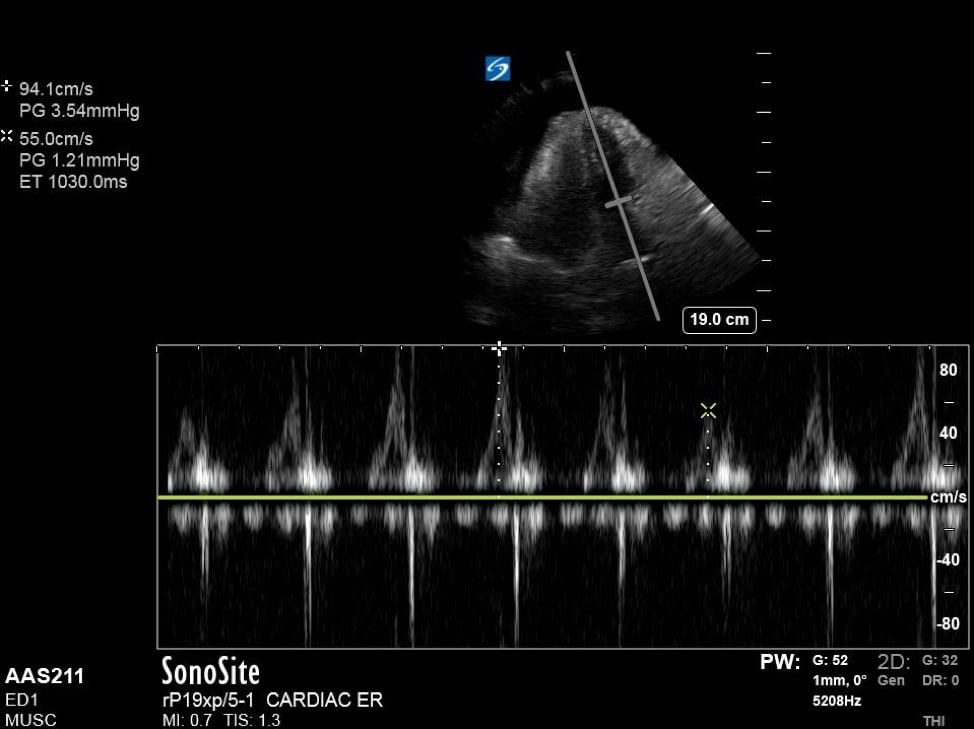

Additionally, when assessing for tamponade, it can be helpful to assess the mitral and tricuspid inflow variation. In pericardial tamponade, there is increased interventricular interdependence during filling exaggerating the respiratory variation flow through the atrioventricular valves. This can be performed in the apical four chamber view, by placing pulse wave doppler (PWD) over the area of either the mitral valve or tricuspid valve. (Figure 4) The velocities are then measured during expiration and inspiration. A mitral valve inflow variation of over 25% or tricuspid valve inflow variation over 40% is indicative of pulsus paradoxus and tamponade physiology. Additional findings in tamponade include a wide, plethoric IVC with minimal variation, as well as collapse of the right atrium during ventricular systole.

Figure 4. Apical 4 chamber view with excessive variation in mitral inflow velocities.